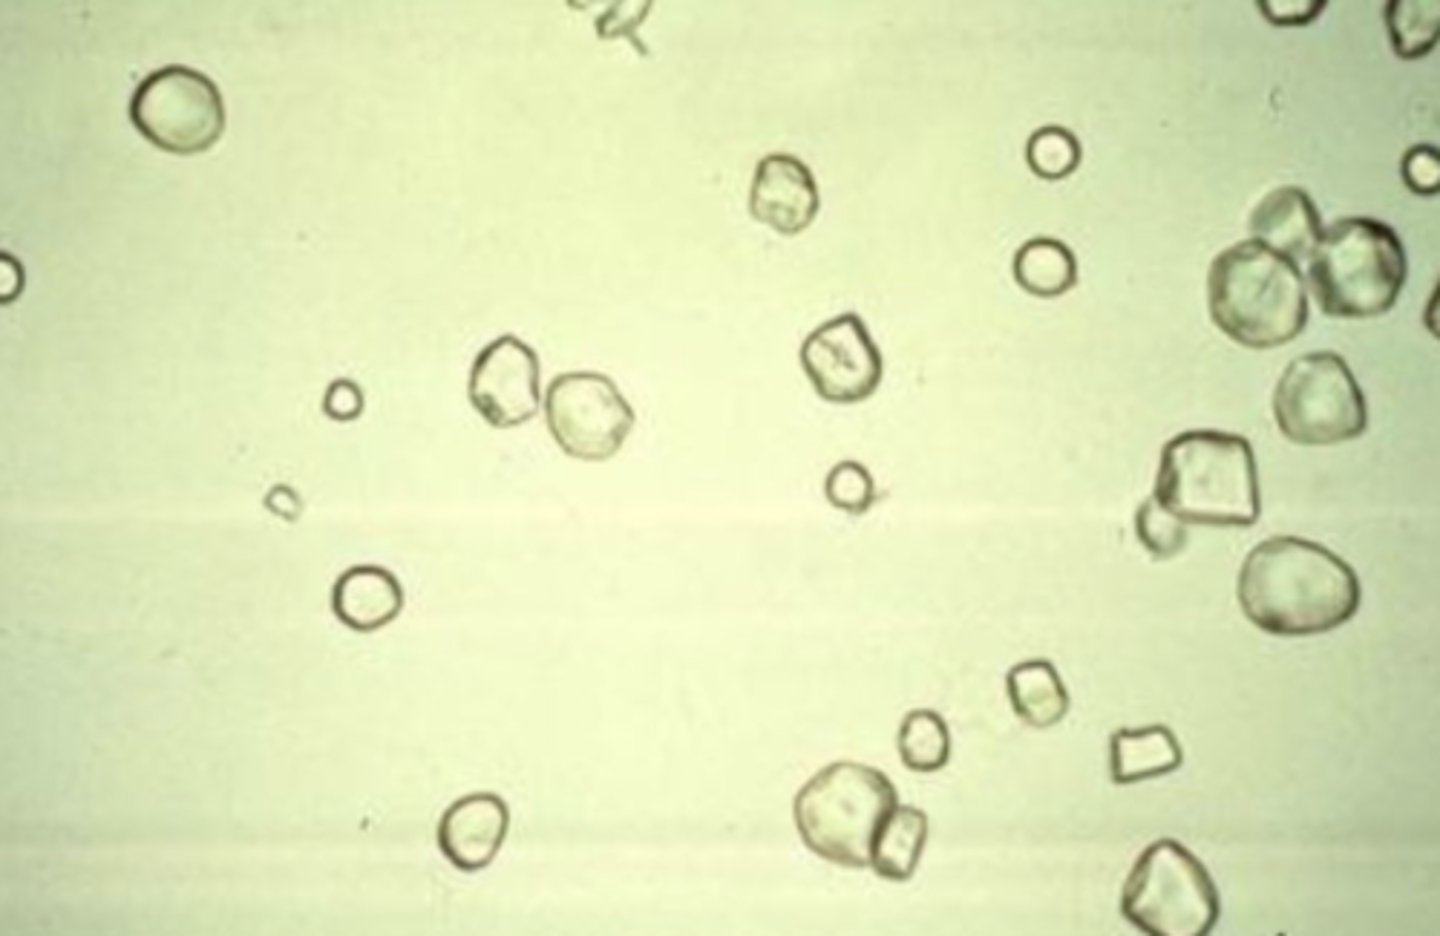

Red Blood Cells

smaller than WBCs but do not have a nucleus. They may be disc- or spherical-shaped or have spiked or crenated appearance. The top image illustrates the disc shape and crenated appearance. associated with damage to the glomerular membrane or vascular injury within the genitourinary tract.

<p>smaller than WBCs but do not have a nucleus. They may be disc- or spherical-shaped or have spiked or crenated appearance. The top image illustrates the disc shape and crenated appearance. associated with damage to the glomerular membrane or vascular injury within the genitourinary tract.</p>

Crenated Red Cells

appears when urine is too concentrated

<p>appears when urine is too concentrated</p>